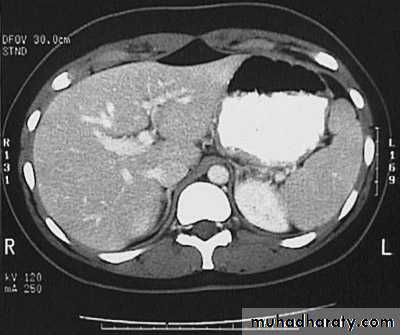

Secondary metastasis in the liver

Multiple rounded hypo density areas of different density , shape & different size .

Pattern of enhancement is either uniform , target or bulls eye pattern .

Hepato megaly .

Secondary metastasis within the liver